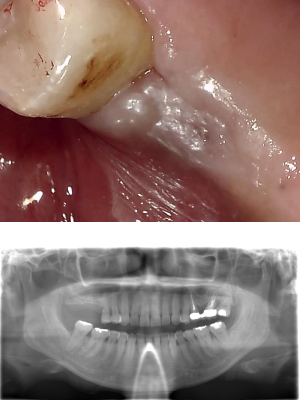

50代 女性 前歯 インプラント抜歯即時・GBR

| 年代・性別 | 50代・女性 |

|---|---|

| 主訴 | 歯の根っこが折れているため、抜歯が必要になり、その後インプラント治療を希望された。 |

| 部位 | 左上1 |

| 治療期間 | 8ヶ月 |

| 費用 | ¥484,000(税込) |

| 副作用・リスク |

|